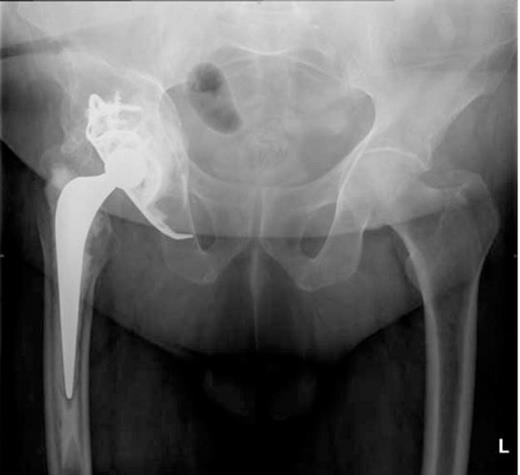

A post-operative radiograph (Figure 1) revealed medial migration of the acetabular construct prompting CT scans of his pelvis.

A pelvic radiograph showing migration of the acetabular construct